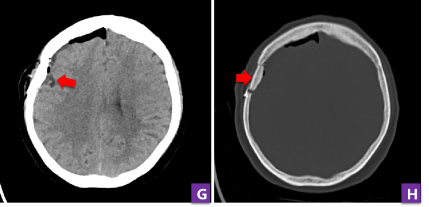

患者增强MRI提示肿瘤均匀强化,起源于硬脑膜

该患者因为头晕来到张培海的诊间寻求帮助。完善头颅CT与磁共振检查后,结果显示颅内存在一个2cm左右、起源于脑膜的良性肿瘤——脑膜瘤。“患者的脑膜瘤虽小,但却临近大脑皮层功能区,如果不及时手术,肿瘤会持续生长造成偏瘫、癫痫等。”张培海说,“但正因为肿瘤不大,如何精准定位是手术的难点。”

开颅后4小时复查头CT,提示肿瘤切除彻底,无出血,骨瓣复位良好